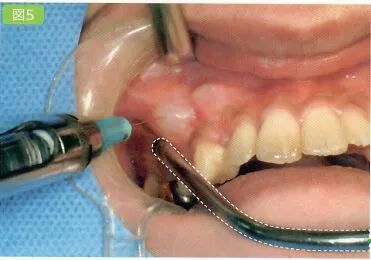

2 浸润麻醉

对手术区域进行浸润麻醉

手术区域包括患牙的颊舌侧的牙龈槽粘膜以及邻牙。一定要避免这些区域的遮挡物。

吸唾器的操作目的

避免患者的舌头部分接触到麻醉药物

临床手术过程中如果患者的舌头接触到麻醉药物的话(利多卡因盐酸盐,阿替卡因盐酸盐等),往往会造成患者口腔内的不适感,临床表现为苦涩感。在一些重度牙周病的情况下,麻醉剂甚至会从龈沟内溢出。

吸引针刺部位溢出的麻醉药物

虚线部分为吸唾管